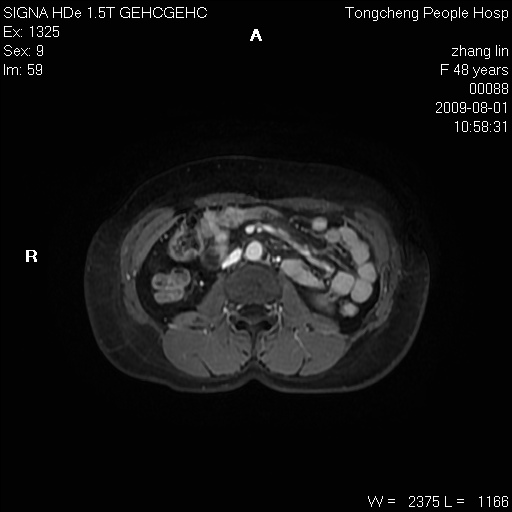

女,48岁。健康体检,彩超发现右肾占位性病变。平素健康。

临床诊断:右肾占位性病变,性质待定(囊肿?肿瘤?)。

上中腹部mr平扫+增强扫描,图像如下:

右肾上极见一类圆形病灶,t1wi呈等信号t2wi呈等高混杂信号,三期增强无强化,边界清---考虑囊肿出血。

同反相位均表现为等信号,病变无强化,考虑含蛋白的囊肿可能,弥散加权相或许有些帮助,

慢性胆囊炎